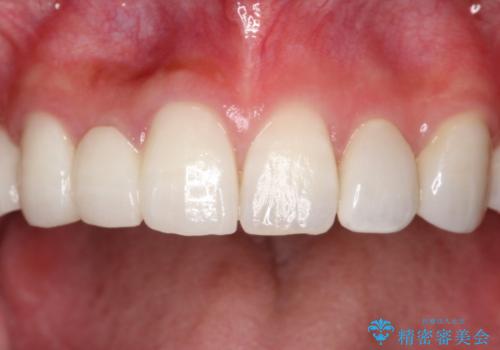

オールセラミックによるやりかえを行いました。

色調もまわりの歯に合わせて、形態も患者様のご希望に沿うように製作させていただきました。